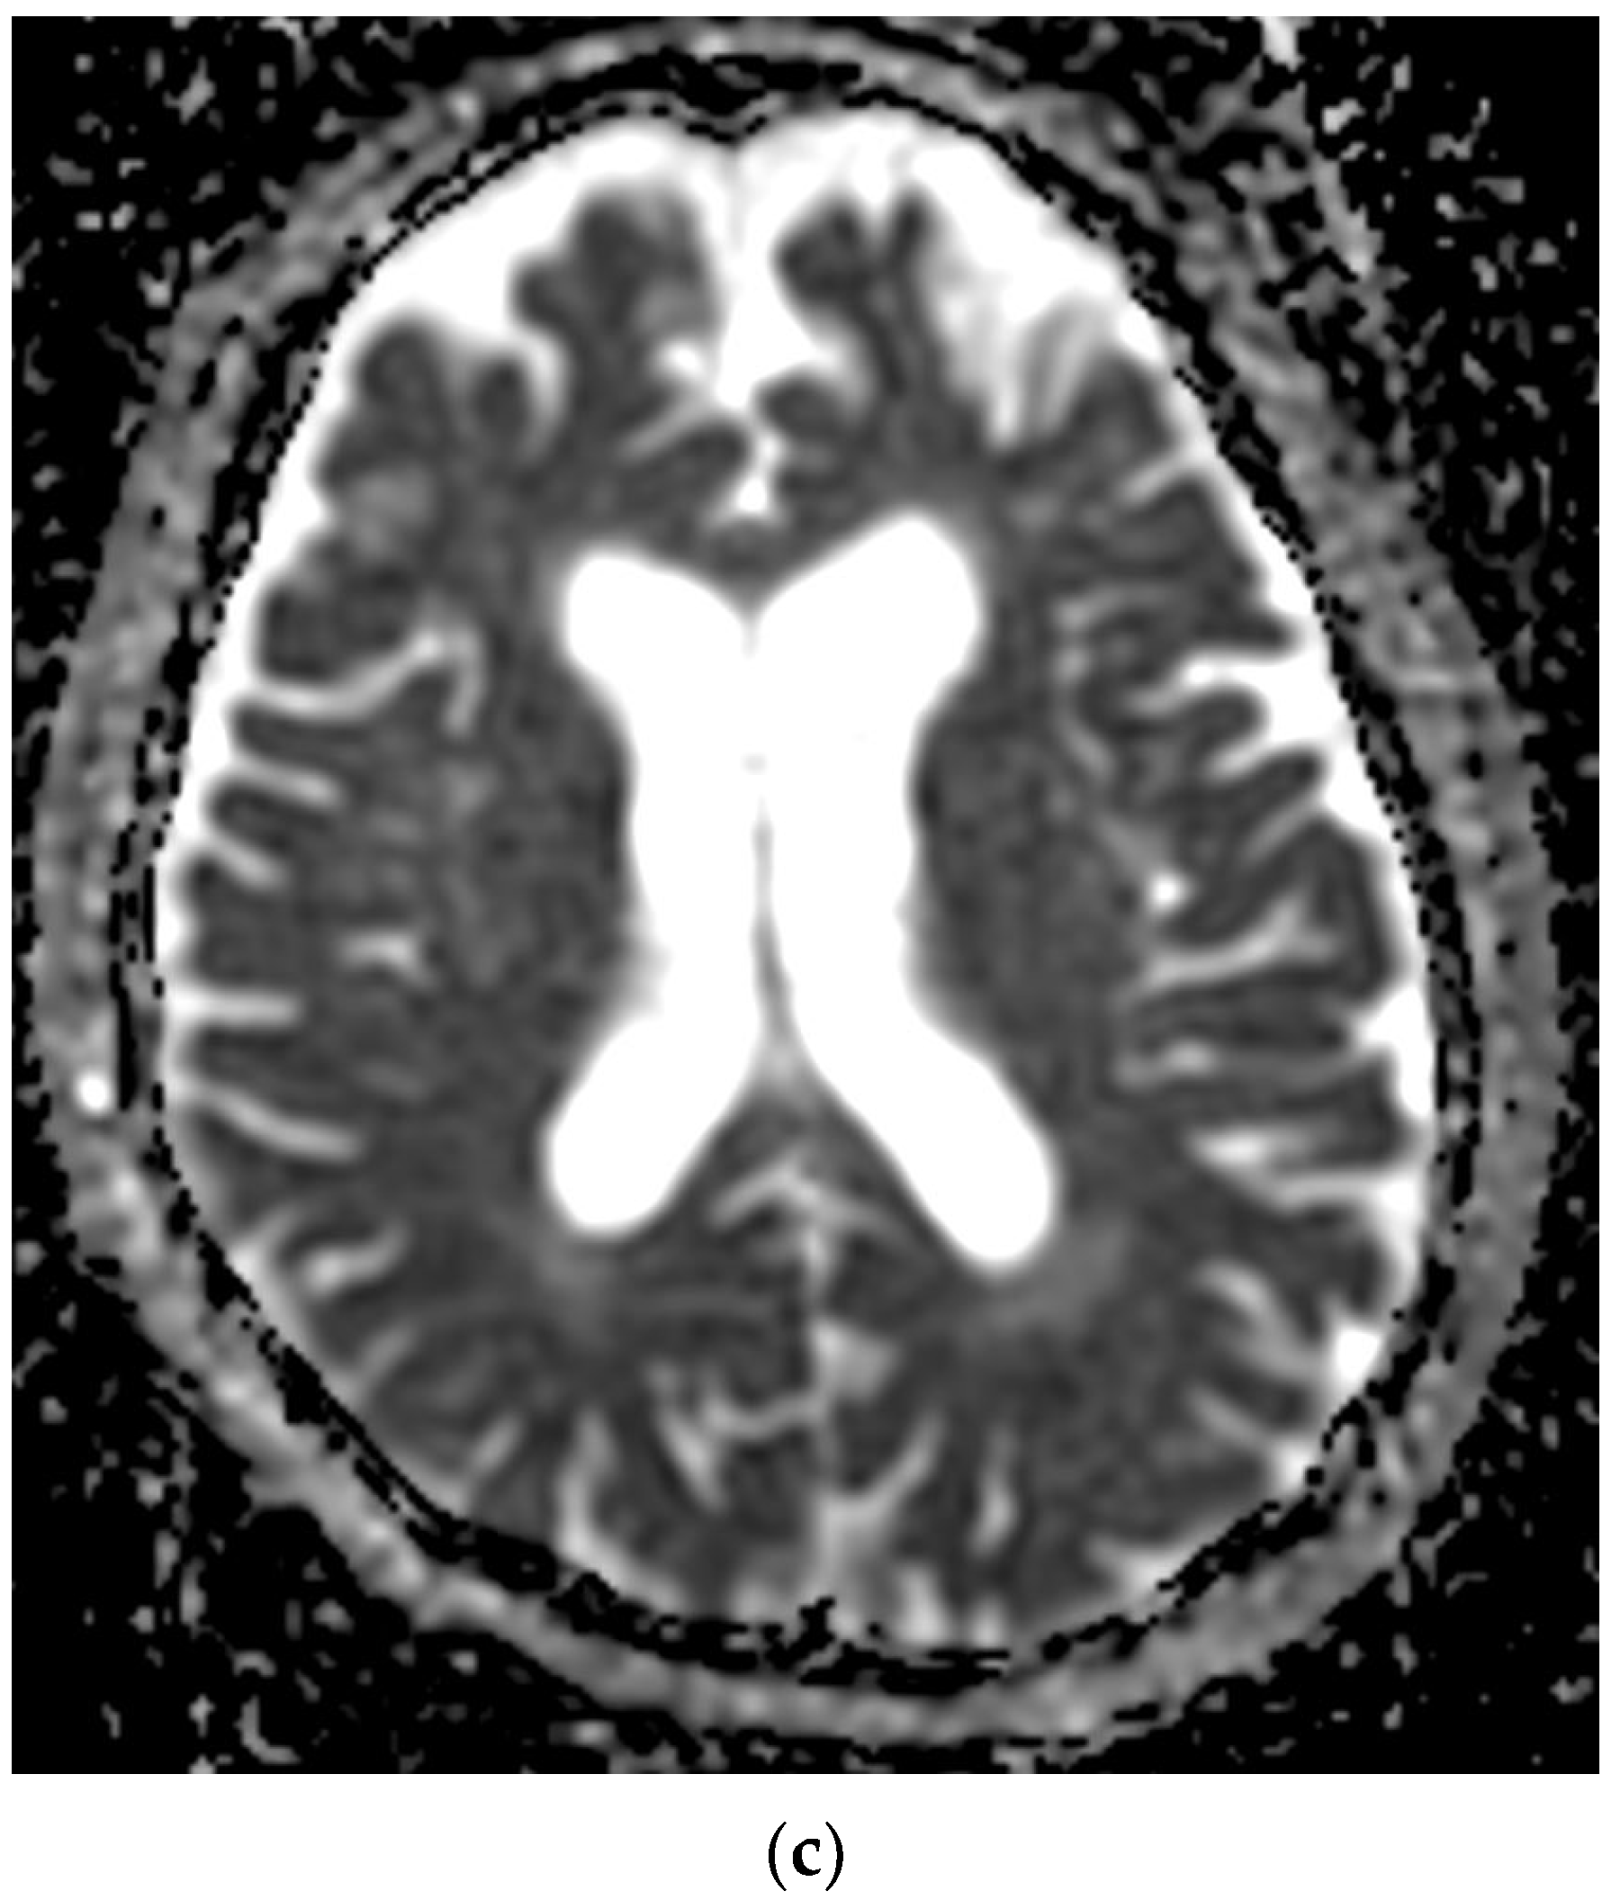

Figure 14. After 11 days from the first pulmonary CT, the cranio-cerebral MRI in the Case 10 patient showed foreshadowing of intense T2 signal (a), with deposits of predominantly peripheral methemoglobin (b), deficient restriction of diffusion (c,d) and gyriform gadolinium I (e), developed in the cortical–subcortical–occipital left median side with extension in the thalamic nucleus on the same part. In conclusion, infarction hemorrhagically transformed into superficial and profound territories of the left posterior cerebral artery.